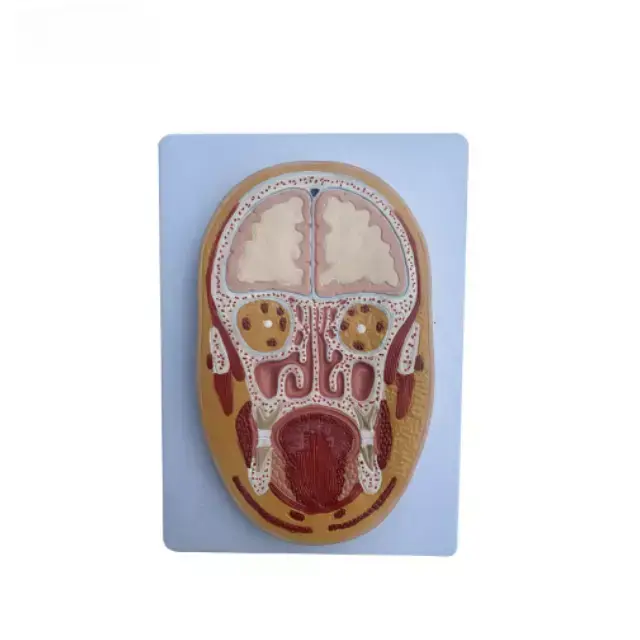

Sección Frontal Media de la Cabeza Serie

Descripcion general